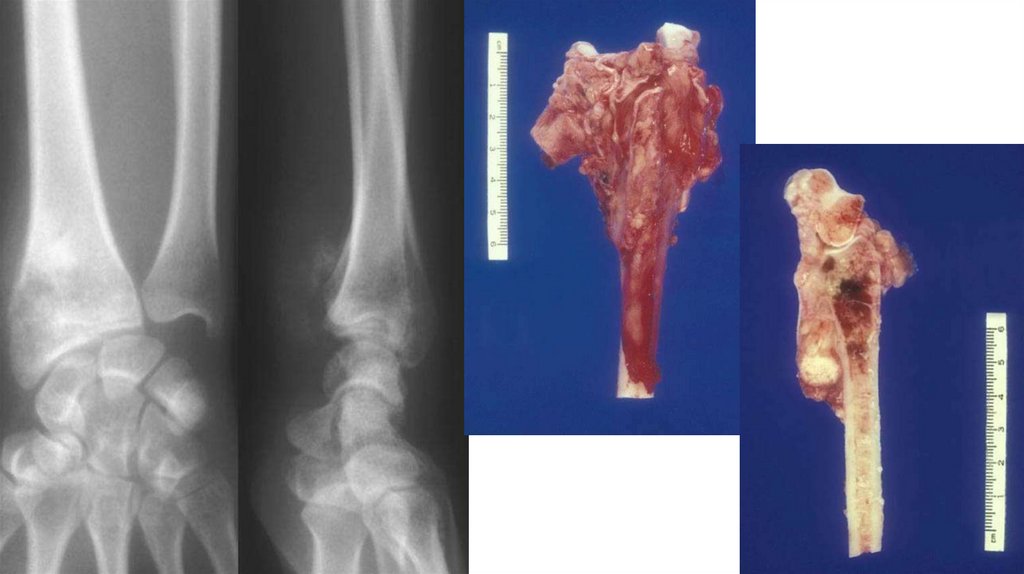

Диагностика

• Рентгенография (очаг деструкции, игольчатый периостит,

«козырек» Кодмана)

• КТ

• МРТ с контрастированием

• Сцинтиграфия с технецием

• Биопсия (высокий полиморфизм с наличием большого количества

митозов, наличие новообразованных остеоидных структур)

• Поиск метастазов